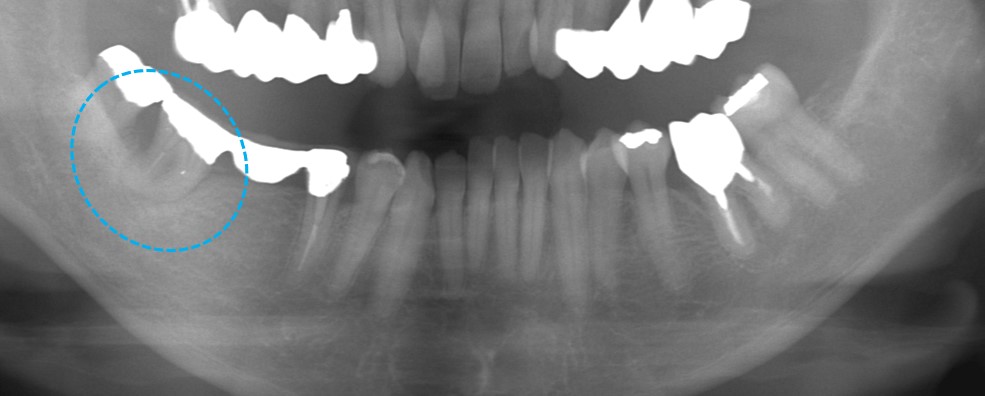

親知らずの移植直後の状態です。この後、根管治療を行いました。

移植後数カ月の写真です。ブリッジを装着して予後良好です。